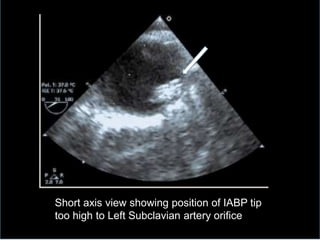

Short axis view of descending aorta

showing origin of left subclavian artery

Short axis view showing position of IABP tip

too high to Left Subclavian artery orifice